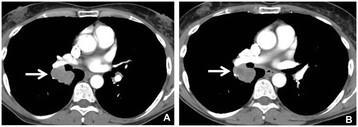

A 61-year-old male with metastatic melanoma. Contrast-enhanced CT scan of the chest at baseline (A) demonstrate a lobulated right lower lobe mass measuring 37 mm and 54.3 HU (A, arrow). The follow-up scan (B) at 11.4 weeks of ipilimumab and bevacizumab therapy demonstrated the lesion measuring 36 mm and 44.4 HU (B, arrow). While the percent decrease of diameter was only 2%, CT density decreased by 18% comparing to baseline, meeting the Choi response criteria.